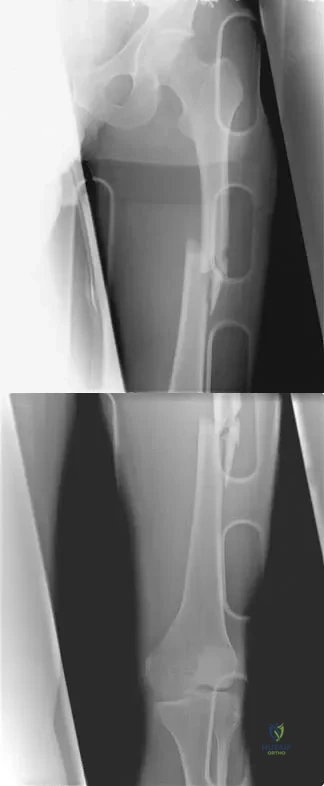

Figure 38 shows the radiograph of a 40-year-old woman who reports severe groin pain and lack of motion of the right hip. History reveals that the patient underwent a femoral osteotomy for hip dysplasia approximately 30 years ago. Treatment should include

Although the patient is young, a total hip arthroplasty will provide pain relief and improve her range of motion. The arthritis is too advanced for the patient to benefit from an osteotomy. In addition, periacetabular osteotomy and hip arthrodesis do not improve range of motion of the hip. It has not been established that patients with severe osteoarthritis will benefit from arthroscopic debridement of the hip.